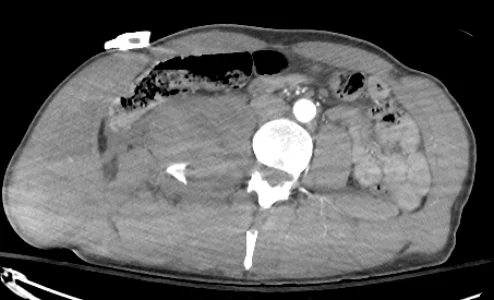

trauma embolization: case 1

42 year old patient with back pain s/p MVA.